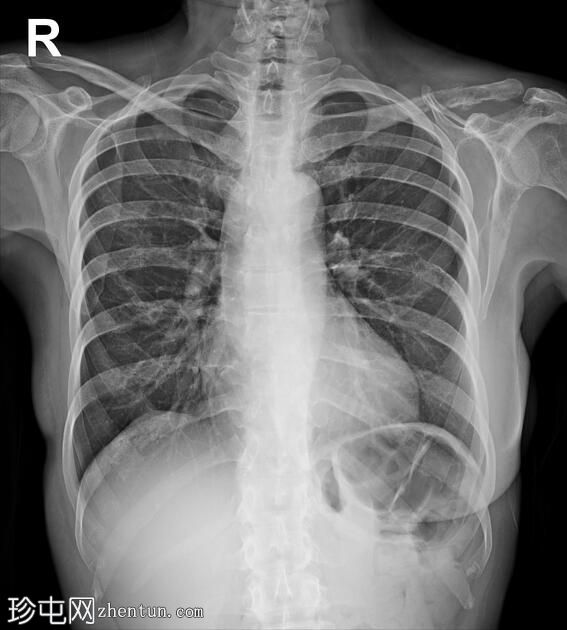

已知乳腺癌脑转移病例。现因胸痛就诊。

年龄:50岁

性别:女

X线片

左侧第7肋后弓及锁骨外侧三分之一处可见溶骨

性病

变,提示骨转移。

右侧乳房切除术。

肺

部听诊清晰。

心脏

大小正常。

X线检查结果提示,该患者既往有右侧乳腺癌病史及乳房切除术,此次X线检查提示溶骨性骨转移。